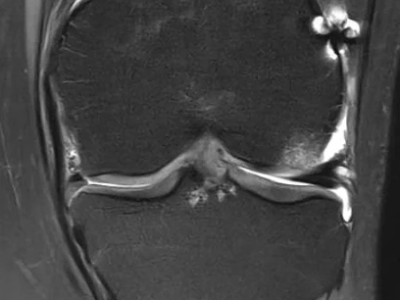

Was Sie zur Meniskustransplantation wissen sollten

Verliert ein junger Mensch den Meniskus, leidet oft die Lebensqualität erheblich. Eine bewährte Behandlungsmethode ist die Meniskusallografttransplantation (MAT). Diese Arbeit bietet Ihnen eine Übersicht, worauf Sie beim Anwenden dieser Methode und der Nachsorge achten sollten.

Pincer-Konstellation, Hüftdysplasie und CAM-Impingement im Röntgenbild/© Fehske K / all rights reserved Springer Medizin Verlag GmbH, Sonographiequerschnitt über der Hälfte des M. quadriceps (Normalbefund)/© Gehlen M et al. / all rights reserved Springer Medizin Verlag GmbH, Mediale Meniskusallografttransplantation /© Winkler PW et al. doi.org/10.1007/s43205-025-00320-y unter CC-BY 4.0, Sehnentransplantate zur Rekonstruktion des vorderen Kreuzbands /© Fink C et al. doi.org/10.1007/s00113-025-01551-4 unter CC-BY 4.0, Knie-MRT zeigt überlastungsbedingte Knochenmarködeme/© Brockmeyer M et al. / all rights reserved Springer Medizin Verlag GmbH, Läufer umfasst sein Sprunggelenk/© PeopleImages / Getty Images / iStock (Symbolbild mit Fotomodell), Gruppe beim Rückentraining im Fitnesscenter/© Robert Kneschke / stock.adobe.com (Symbolbild mit Fotomodellen), Walking mit Kniebandage/© Suzi Media Production / Getty Images / iStock (Symbolbild mit Fotomodell), Vordere Kreuzbandruptur/© Springer-Verlag Berlin Heidelberg 2016, Operation zum Kniegelenkersatz/© Issara / stock.adobe.com, Ein kleines Kind hüpft auf einem Trampolin/© anzebizjan / stock.adobe.com (Symbolbild mit Fotomodellen), Anteriore Schulterluxation im Röntgenbild/© Spagna G et al. / all rights reserved Springer Medizin Verlag GmbH, Laufschuh binden/© ssoil322 / stock.adobe.com, Hämatom an der Stirn des 9-Jährigen/© Dr. med. Thomas Hoppen, Innenseitige Hauteinziehung bei eingeschlagenem Innenband/© Akalin ER et al. / all rights reserved Springer Medizin Verlag GmbH, Rekonstruktion der Halswirbelsäule im CT/© Prof. Klaus Schunk, Sonografie am Fußgelenk/© A. Schuh, Gebrochener Fuß im Gips/© Aleksandr Kirillov / stock.adobe.com (Symbolbild mit Fotomodell), Search Icon, Arthropedia, Frau unkenntlich fasst sich ans Knie/© Pornpak Khunatorn / Getty Images / iStock (Symbolbild mit Fotomodell), Ärzteteam führt Hüftoperation durch/© ATRPhoto / stock.adobe.com (Symbolbild mit Fotomodell)